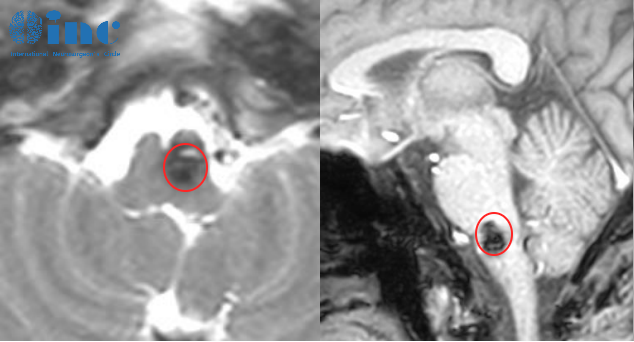

六天后,2021年10月21日。“醫(yī)生,這是什么病?”診室里,他的聲音有些發(fā)緊。報(bào)告單上幾個(gè)黑體字張牙舞爪。那些分開都認(rèn)識(shí)的漢字,組合成了一句他聽不懂的判決書:延髓海綿狀血管瘤伴出血。

延髓海綿狀血管瘤伴出血

2022年9月,復(fù)查MRI,面對(duì)這個(gè)“無(wú)法手術(shù)”的病灶,醫(yī)生建議伽馬刀。